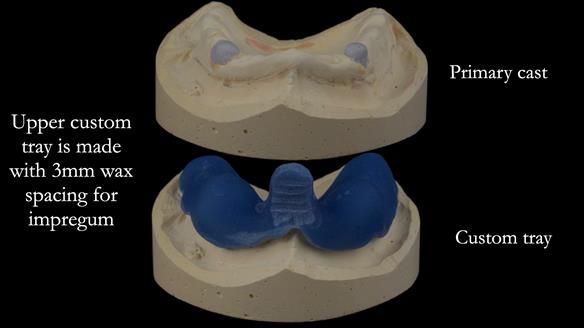

The detailed clinical situation and treatment process are outlined below, with clinical work provided by me and technical work by Rowan Garstang. New complete implant supported complete dentures were made. The new upper denture had ‘almost’ full palatal extension for the non-splinted implants following ITI guidelines. A decision was reached to retain the worn Kerator attachments, as their removal could potentially accelerate implant failure. The treatment spanned five visits for denture fitting and one review. Alisdair expressed great satisfaction with the treatment, noting a significant enhancement in his overall quality of life.